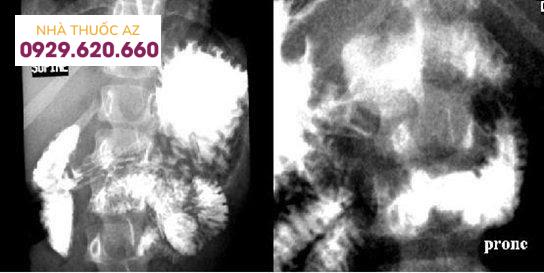

Soi và chụp tá tràng có cản quang ghi nhận: Dãn tá tràng D1 và D2. Chèn ép từ bên ngoài vào tá tràng D3. Tăng nhu động đoạn trên bị chèn ép và lưu thông từ dạ dày xuống tá tràng chậm. Giảm sự tắc nghẽn khi thay đổi tư thế.

X quang uống thuốc cản quang của bệnh nhân này: dãn dạ dày và tá tràng trên D3, xẹp D3 ngay mức giữa ĐM chủ bụng.

Giãn dạ dày và tá tràng đến đoạn giữa ĐMTTT và ĐM chủ bụng. Tá tràng D3 bị chèn ép xẹp lép bởi hẹp góc ĐMTTT – ĐM chủ bụng ở hai bệnh nhân khác nhau (hình A và B)

Hội chứng ĐM TTT ở do bị vẹo cột sống ra trước gây hẹp góc. Nguồn: Michael R Federle. SMA syndrome. In: Michael R Federle. Diagnostic imaging: Abdomen. Amirsys 2010: I-4-14